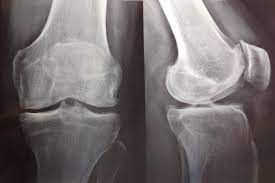

Pérdida de peso inducida por medicamentos contra la obesidad y mortalidad por todas las causas en pacientes con osteoartritis de rodilla o cadera

07 diciembre 2023

En este estudio poblacional, una tasa de pérdida de peso lenta a moderada, pero no rápida, inducida por medicamentos contra la obesidad se asocia con un menor riesgo de mortalidad por todas las causas en personas con sobrepeso u obesidad y artrosis de rodilla o cadera. Arthritis Rheumatol. 6 de diciembre de 2023